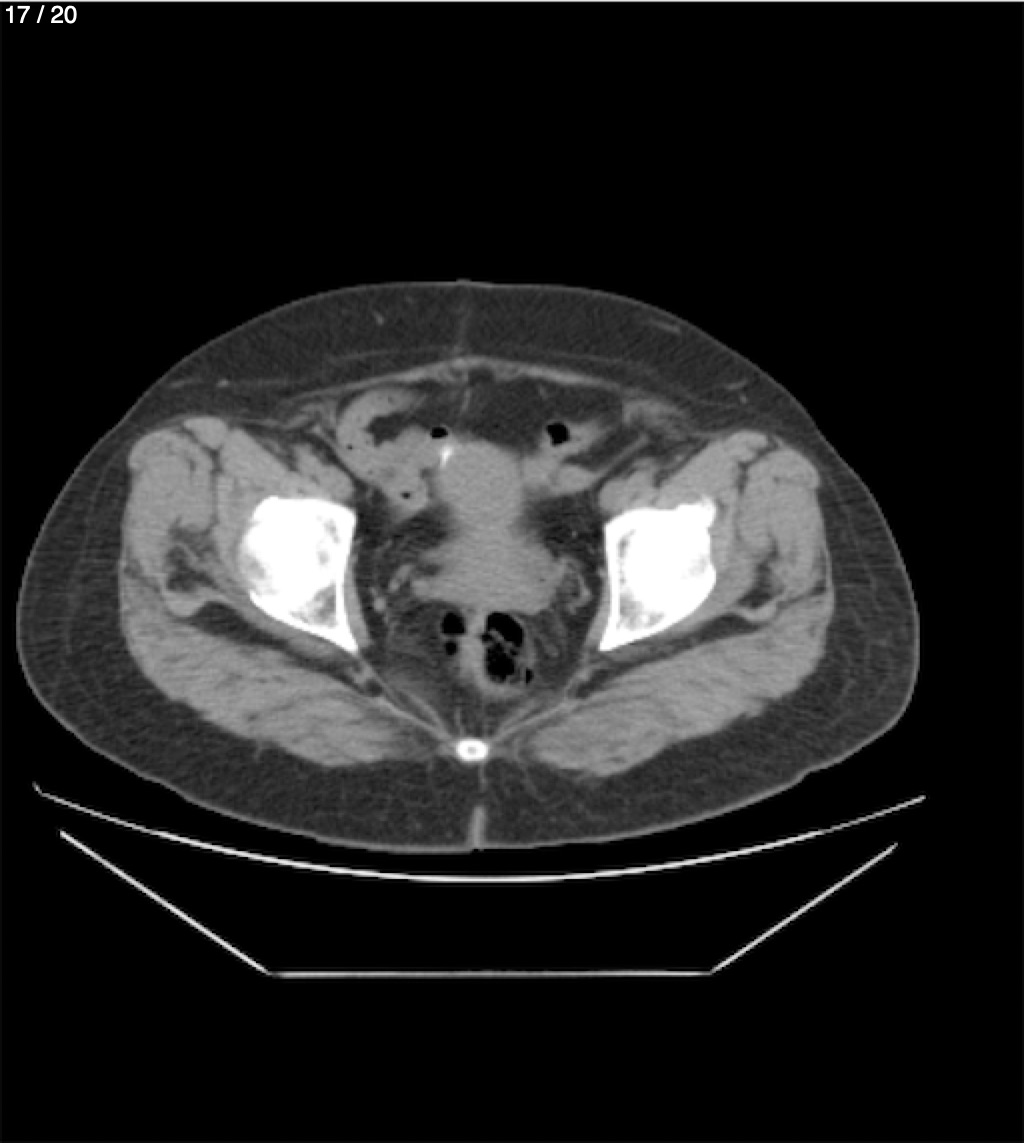

Maria Enrique Giron Dominguez63A - T.C Abdomen Simple